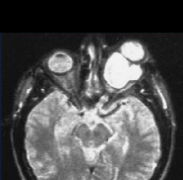

磁共振成像(MRI)是有用的迅速识别这些病理,以避免长期性视力丧失。在T2W图像上,显示中央等强度,周围高强度对应于神经周围蛛网膜神经胶质瘤。图3:NF1患者视神经胶质瘤。图...